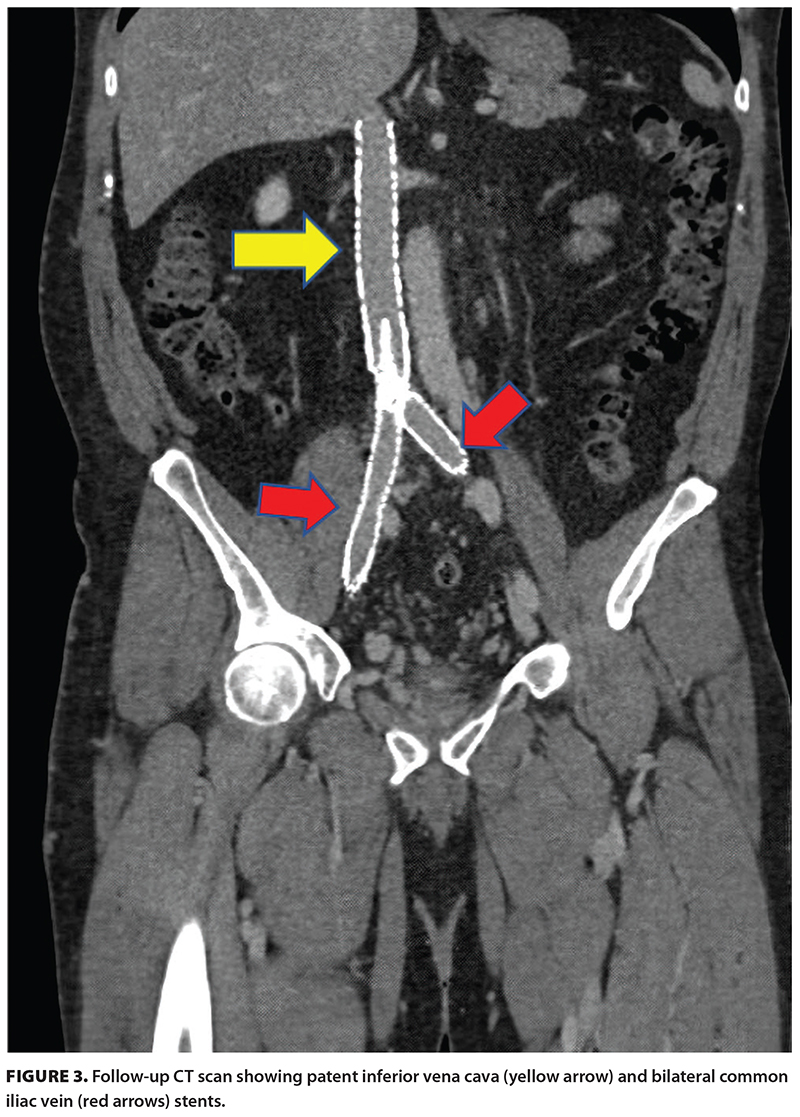

A 46-year-old patient was diagnosed with stage 4 non-Hodgkin lymphoma after presenting with a large nodal conglomerate retroperitoneal mass. They subsequently underwent an extended course of chemoimmunotherapy for the treatment of their lymphoma. However, the retroperitoneal mass caused compression on adjacent vasculature and resulted in occlusive thrombus formation within the deep venous system, extending from the inferior vena cava to the ankles [Figure 1]. This required therapeutically dosed anticoagulation, and although the lymphoma went into remission, the thrombus remained. The patient developed significant postthrombotic syndrome as a result of this residual thrombus and experienced symptoms of chronic swelling, pain, heaviness, and, most importantly, venous claudication. These symptoms significantly impacted their quality of life, because daily activities such as walking short distances and exercising were intolerable. Their symptom severity correlated with a severe Villalta score of 22.

The patient’s CT scan showed chronic occlusion of the infrarenal inferior vena cava and bilateral iliac system, with extensive pelvic, paralumbar, retroperitoneal, and abdominal wall venous collaterals. The patient’s hematologist consulted interventional radiology for endovascular management options. After a detailed discussion of the proposed procedural intervention, the importance of postprocedural antithrombotics, and long-term follow-up, the patient was keen to proceed.